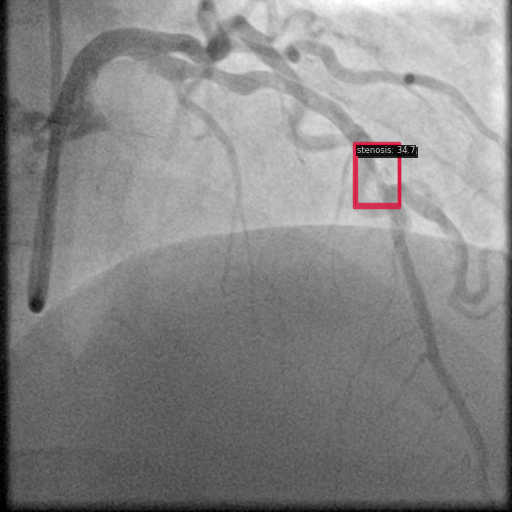

图7 YOLO 检测显示多个具有置信度分数的检测区域。

3.3 YOLO 检测模式

YOLO 通过有效捕获解剖结构同时保持相对高的置信度分数提供了合理的权衡。与基于 transformer 的模型相比,它对小型狭窄区域的检测更好。

如图 7 和图 10 所示,YOLO 的检测模式通常包括具有不同置信度分数的多个区域。这种方法为临床应用提供了精度与召回率之间的合理平衡。

图10 YOLO 检测显示多个具有置信度分数的检测区域。